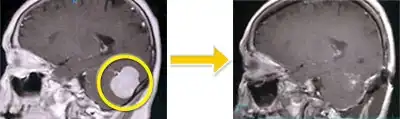

髄膜腫-4 右蝶形骨縁髄膜腫(外側型)

頭痛の精査でみつかった5cm大の髄膜腫です。右の脳は内側に圧迫されています。 腫瘍は中大脳動脈という大事な血管を巻き込んでいましたのでその部分のみわずかに残してほぼ全摘出しました。手術後、腫瘍によって圧迫されていた脳は本来の位置へ戻っています。